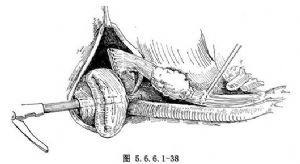

(4)在肿瘤上缘5cm预定切除食管部位,用中圆针穿7号丝线围绕食管纵轴1周做一贯穿食管壁全层的荷包缝线,针距为0.5~0.7cm,暂不打结。如果使用GIA缝合器,即在胃前壁另作一小切口并经此切口装入吻合器主件(图5.6.6.1-38)。